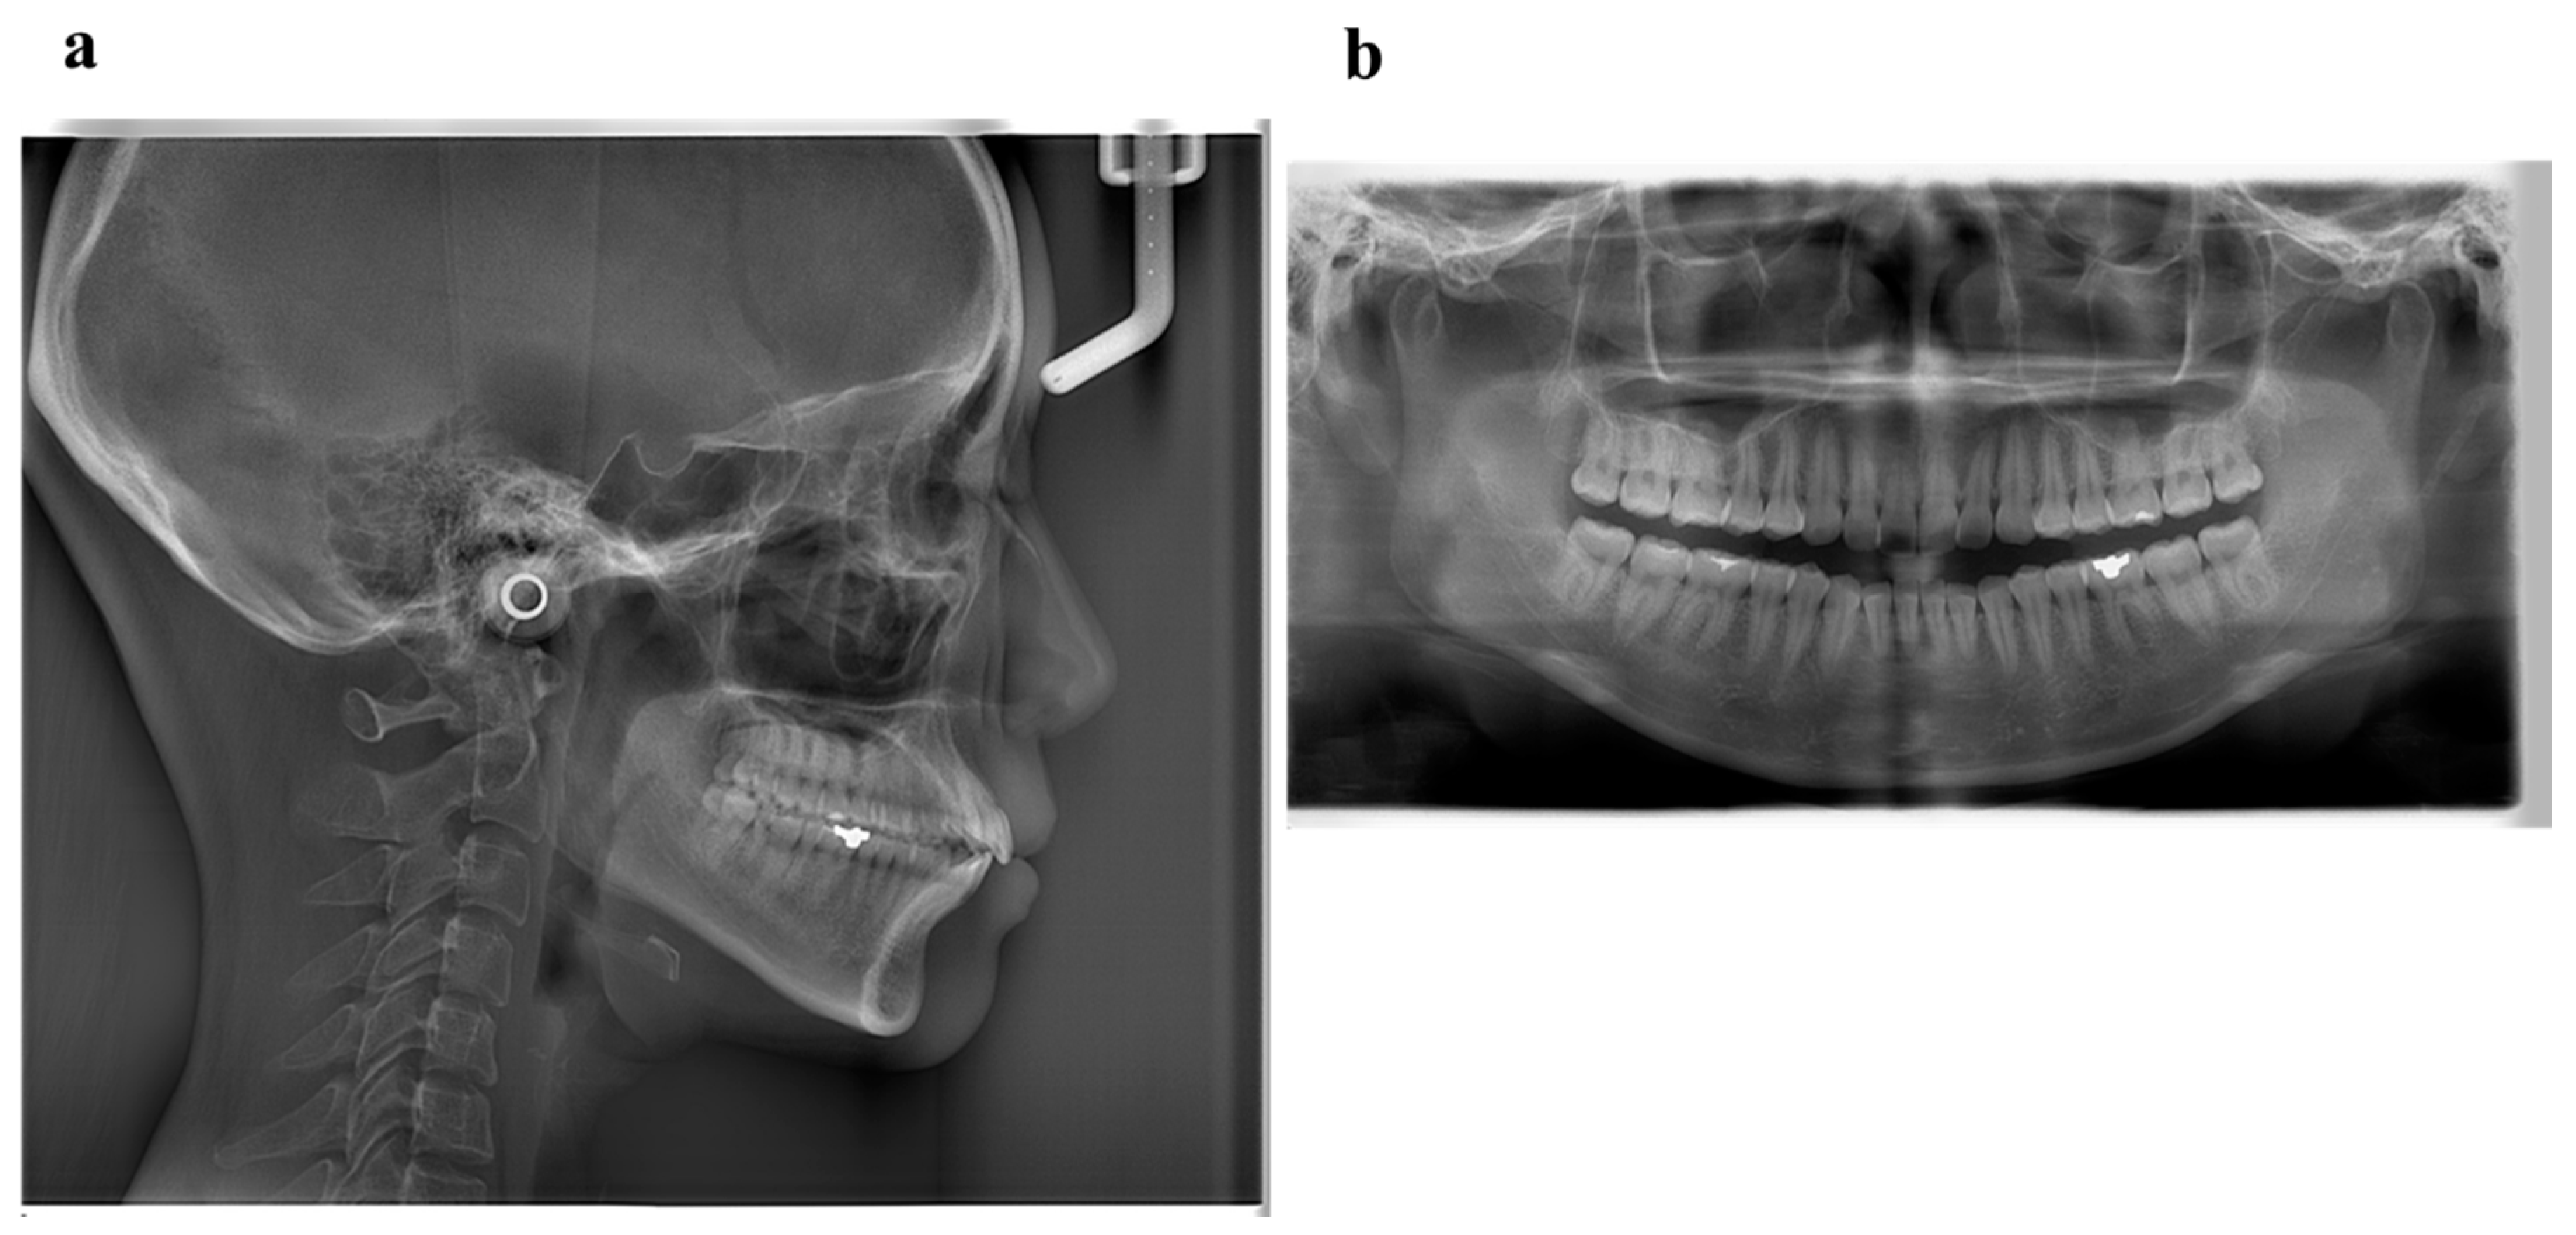

6.1. Diagnosis

6.2. Treatment Objectives

6.3. Treatment Alternatives

6.4. Treatment Progress

6.5. Treatment Results

6.6. Case Summary

| Measurement | Normal (Japanese Woman) | Pretreatment (29 y 19 m) | Posttreatment (31y 2m) |

|---|---|---|---|

| SNA (° ) | 81.3 ± 2.7 | 80.0 | 80.0 |

| SNB (° ) | 78.6 ± 2.7 | 79.5 | 79.0 |

| ANB (° ) | 2.6 ± 1.1 | 0.5 | 1.0 |

| FMA (° ) | 26.3 ± 4.1 | 24.0 | 24.0 |

| FMIA (° ) | 56.9 ± 6.4 | 52.0 | 61.0 |

| IMPA (° ) | 96.8 ± 6.4 | 104.0 | 95.0 |

| U1-FH (° ) | 112.1 ± 4.2 | 126.5 | 115.5 |

| U1-L1 (° ) | 123.5 ± 5.5 | 105.0 | 125.0 |

| U1-A-Pog (mm) | 6.2 ± 1.5 | 11.2 | 4.6 |

| L1-A-Pog (mm) | 3.0 ± 1.5 | 8.1 | 2.3 |

| Gonial angle (° ) | 118.8 ± 6.1 | 117.5 | 117.5 |

| E-line: Upper (mm) | 1.4 ± 2.0 | −0.5 | −2.0 |

| E-line: Lower (mm) | 1.4 ± 2.0 | +0.3 | −0.7 |